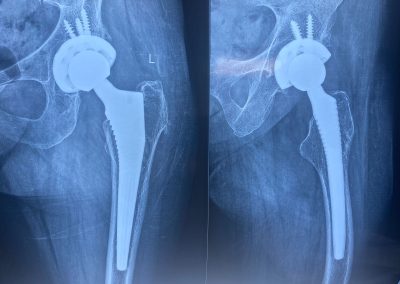

عام ٢٠٢٤ كانت الالام مع المشي اصبحت شديدة مما استدعى عمل تغيير كامل للمفصل

فيديوهات تشرح المريضه حالتها مع فيديو يبين المشي بشكل طبيعي تماما